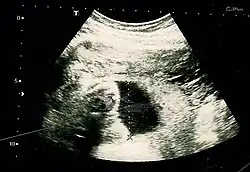

The result of an ultrasonography: a black and white image that shows a clear view of the interior abdomen

A dating scan at 12 weeks

Obstetric ultrasonography is routinely used for dating the gestational age of a pregnancy from the size of the fetus, determine the number of fetuses and placentae, evaluate for an ectopic pregnancy and first trimester bleeding, the most accurate dating being in first trimester before the growth of the foetus has been significantly influenced by other factors.[22] Ultrasound is also used for detecting congenital anomalies (or other foetal anomalies) and determining the biophysical profiles (BPP), which are generally easier to detect in the second trimester when the foetal structures are larger and more developed.[23]

X-rays and computerized tomography (CT) are not used, especially in the first trimester, due to the ionizing radiation, which has teratogenic effects on the foetus.[24] No effects of magnetic resonance imaging (MRI) on the foetus have been demonstrated,[25] but this technique is too expensive for routine observation. Instead, obstetric ultrasonography is the imaging method of choice in the first trimester and throughout the pregnancy, because it emits no radiation, is portable, and allows for realtime imaging.[26]

The safety of frequent ultrasound scanning has not been confirmed. Despite this, increasing numbers of women are choosing to have additional scans for no medical purpose, such as gender scans, 3D and 4D scans.[27] A normal gestation would reveal a gestational sac, yolk sac, and fetal pole.[28]

The gestational age can be assessed by evaluating the mean gestational sac diameter (MGD) before week 6, and the crown-rump length after week 6. Multiple gestation is evaluated by the number of placentae and amniotic sacs present.[29]